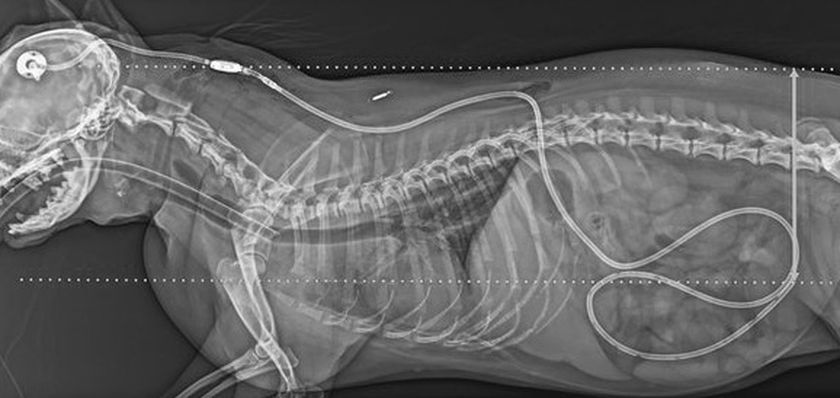

Si le traitement conservateur de l'hydrocéphalie s'avère inefficace ou si l'état du chien est grave, une intervention chirurgicale est nécessaire. La dérivation ventriculo-péritonéale est utilisée à cette fin.

L'objectif de l'intervention est de dilater les voies d'écoulement du liquide céphalo-rachidien et de créer une voie supplémentaire pour son drainage hors des ventricules cérébraux. Un cathéter est inséré dans le ventricule latéral du cerveau par un petit trou de trépanation pratiqué dans le crâne. Il est suturé aux os du crâne, passe sous la peau entre les pattes avant et est introduit dans la cavité abdominale par voie thoracique. Ce cathéter est muni d'une valve de basse pression. Lorsque la pression intracrânienne dépasse un seuil prédéterminé, la valve s'ouvre, permettant ainsi au liquide céphalo-rachidien excédentaire de s'écouler dans la cavité abdominale. Une fois le liquide céphalo-rachidien excédentaire drainé, l'état du chien se stabilise.

Les animaux ayant subi une dérivation ventriculo-péritonéale nécessitent des conditions de vie particulières et des soins attentifs tout au long de leur existence. Leurs propriétaires doivent surveiller constamment le cathéter de drainage afin d'éviter toute obstruction et remplacer ce dispositif, relativement coûteux, si nécessaire. Les jeux actifs et les longues promenades sont proscrits. Même les manipulations doivent être effectuées avec précaution pour éviter le déplacement du tube de drainage.